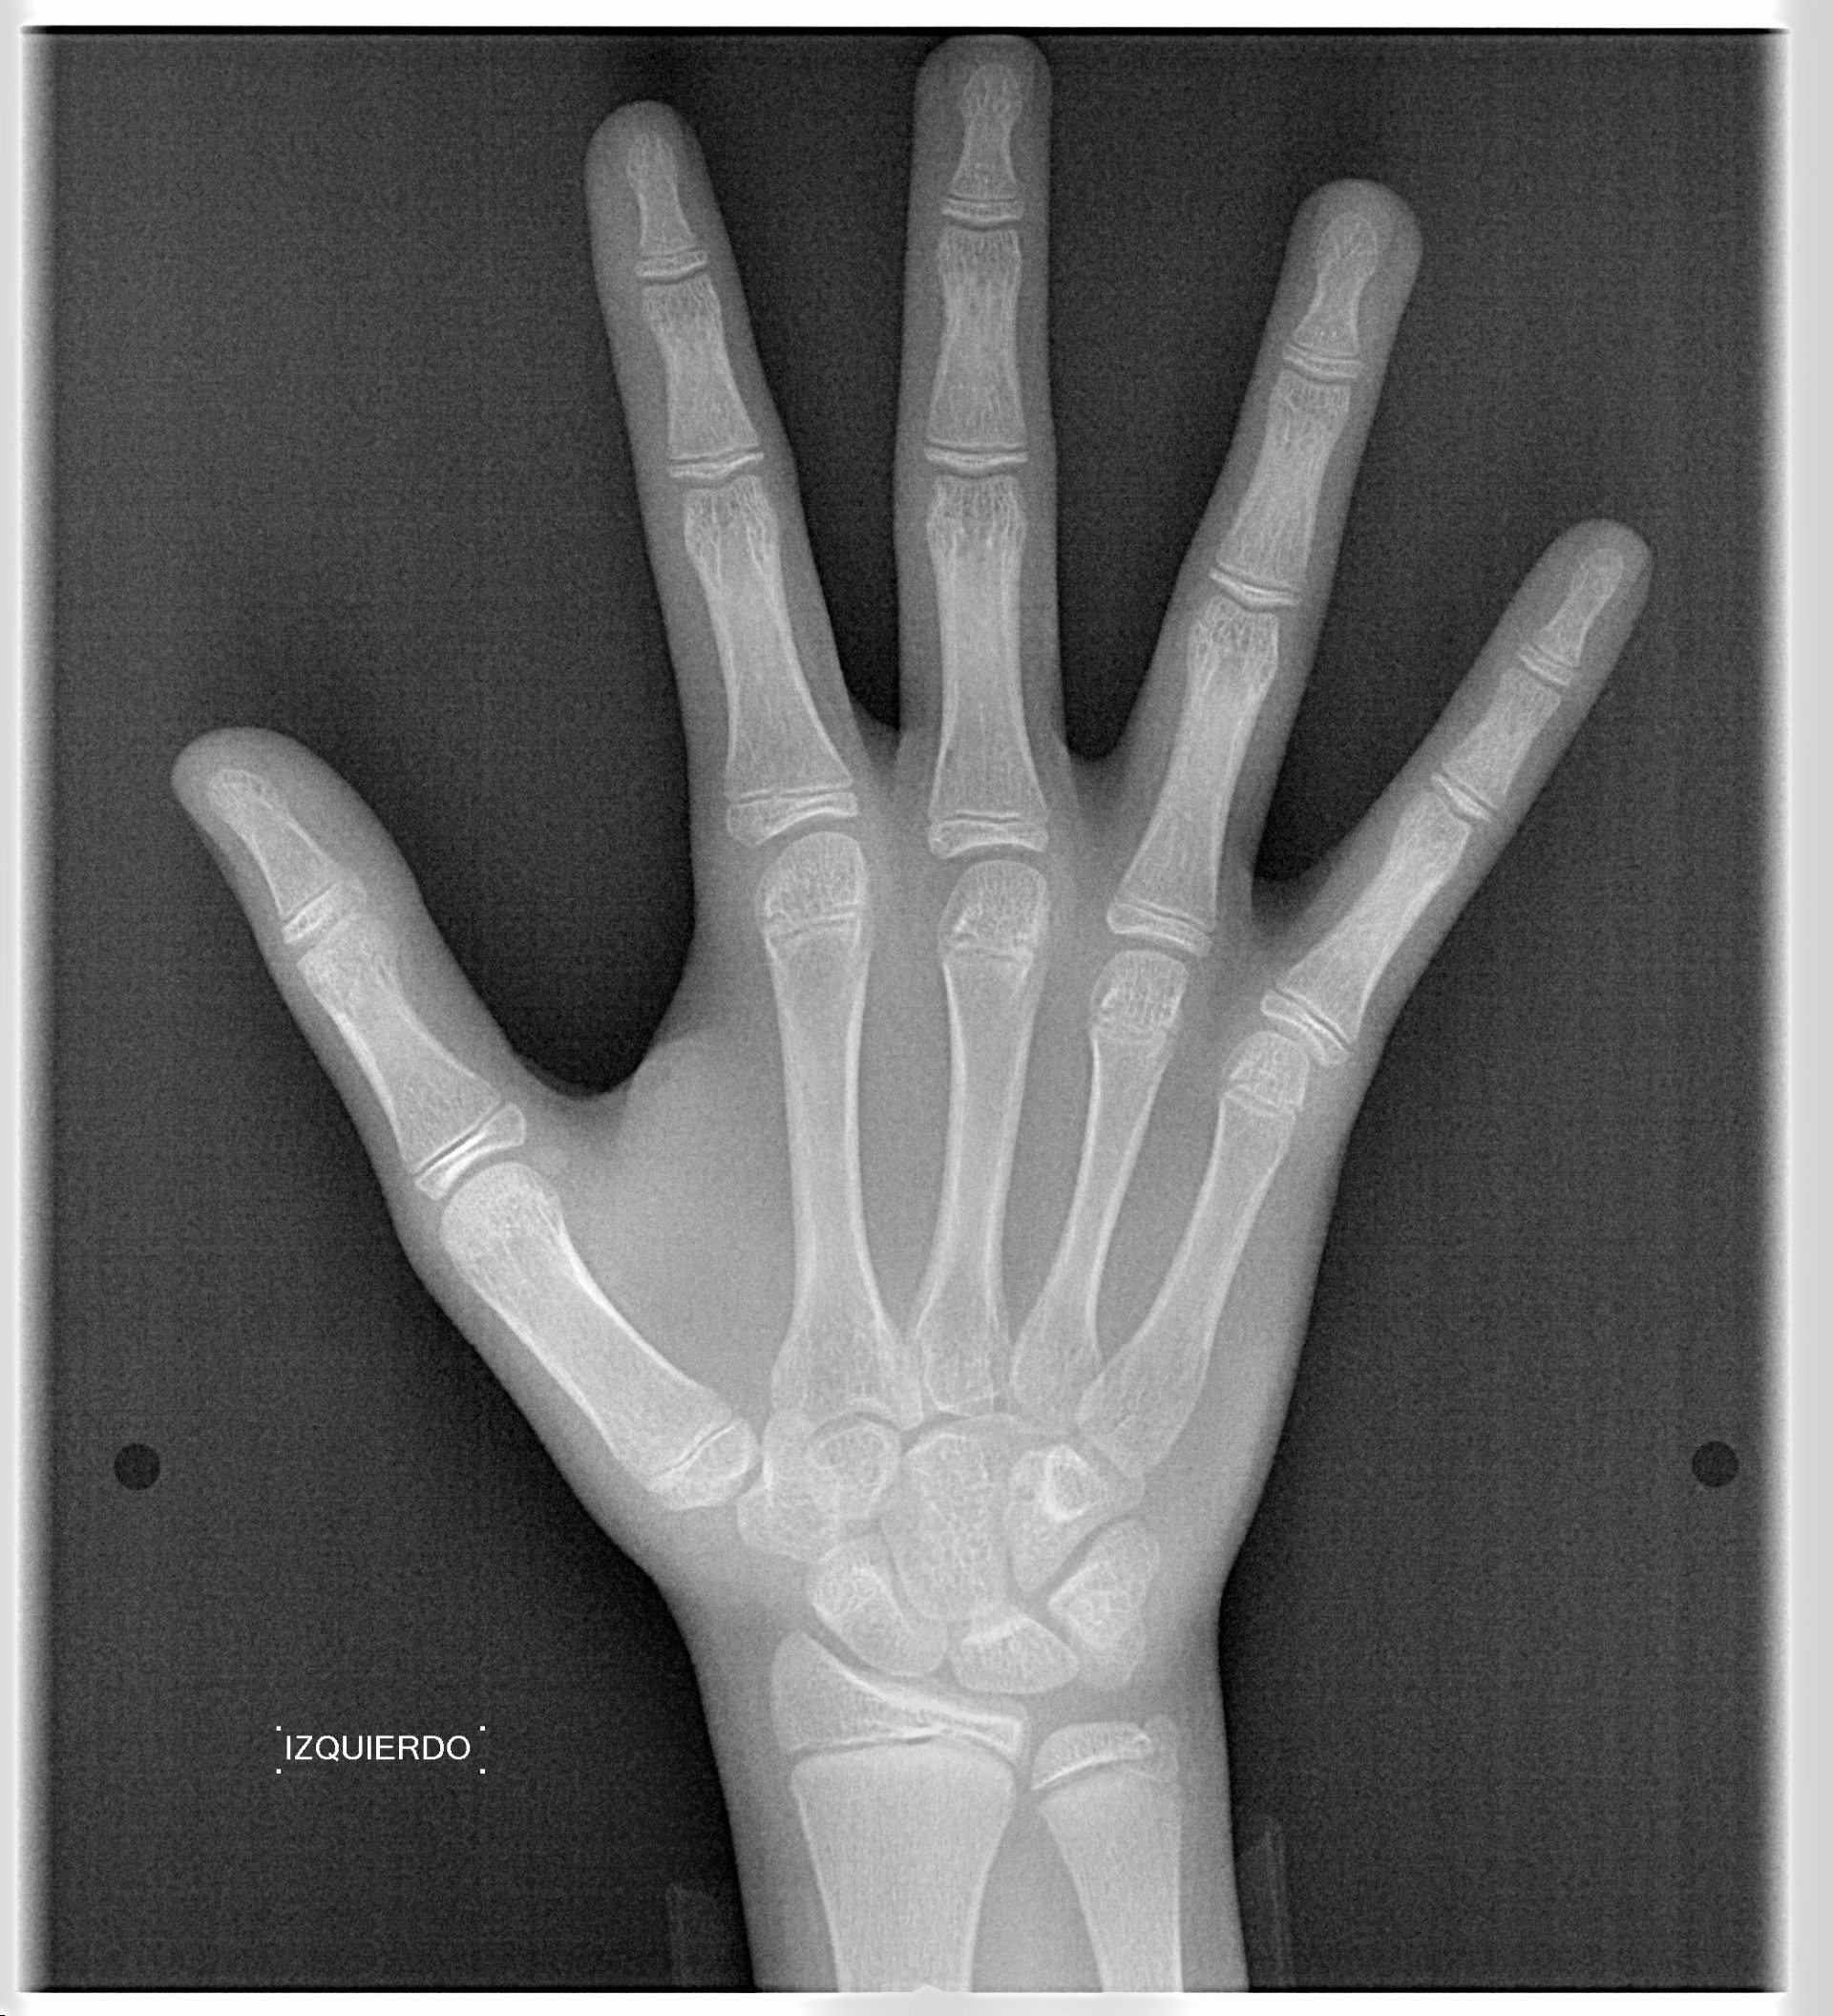

El mayor beneficiado con el uso de esta tecnología es el paciente, el cual podrá ser evaluado en todas sus dimensiones con una baja dosis de radiación, con un costo accesible y sin contaminar  el medio ambiente. Dependiendo de la necesidad del paciente, hay varios tipos de tomografías y los especialistas en el área odontológica hacen uso de ellas según su especialidad.

Planificación de tratamientos ortodónticos y ortognáticos